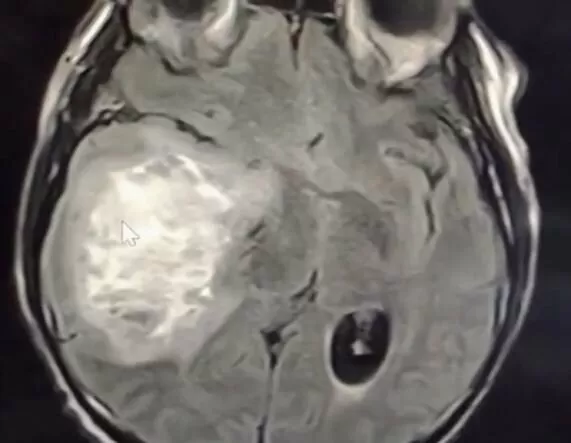

Мультиформна гліобластома. Це найнебезпечніший та найзлоякісніший вид мозкових гліом – 4 ступінь. Характеризується швидким зростанням, проростанням до інших структур мозку (мозочок, таламус, півкулі). Уражає частіше чоловіків старшого віку (середній вік – 56 років).